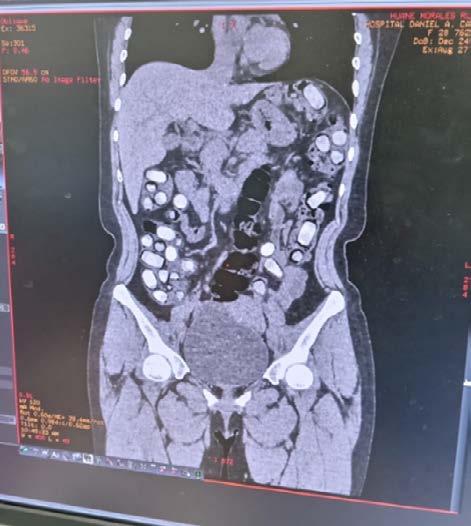

En una operación antidrogas realizada en el Aeropuerto Internacional Jorge Chávez, ubicado en el Callao, efectivos del Departamento Antidrogas detuvieron a dos mujeres que intentaban transportar drogas en la modalidad de “ingesta”.

Las detenidas, identificadas como Nadia Mercedes Vidal Vidal, de 36 años, y Rut Ana Huane Morales, de 28 años, mostraron un evidente nerviosismo mientras esperaban su vuelo con destino a Santiago de Chile en la zona de pago del TUUA (molinete) de salidas internacionales.

Los agentes, tras notar la actitud sospechosa de ambas mujeres, procedieron a realizar un examen de rayos X con el sistema Body Scam, el cual reveló la presencia de “presuntos cuerpos extraños en la cavidad abdominal” de las detenidas.

Ante estos hallazgos, fueron trasladadas de inmediato al hospital Daniel A. Carrión, en Bellavista, para realizarles una tomografía, la cual confirmó la existencia

eIntentaban viajar a Chile con las sustancias dentro de su cavidad abdominal

de objetos extraños en sus cavidades abdominales.

Con conocimiento del representante del Minis -

terio Público, las mujeres fueron puestas bajo custodia policial y permanecen en observación en el área

de Emergencia del nosocomio.

Además de la droga, se les incautaron dos celula-

res, 1700 euros, 2 dólares y 50 soles, que ahora forman parte de la investigación en curso.